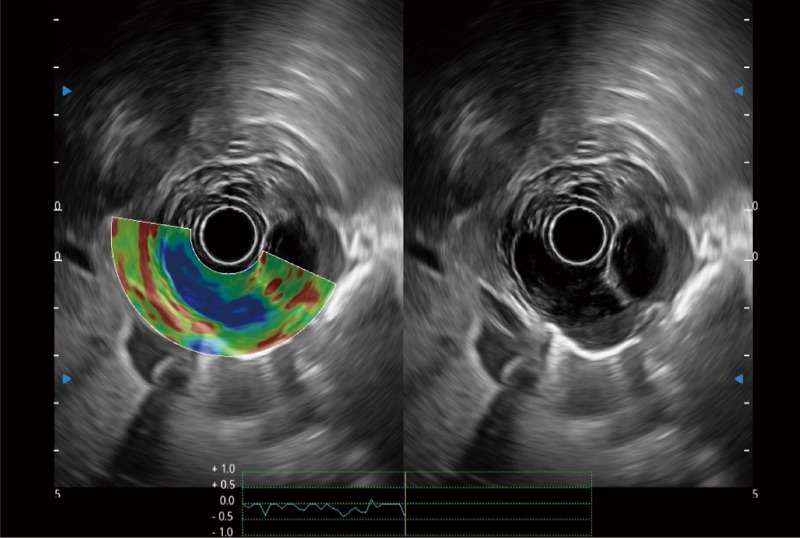

位移矯正技術(shù)

不可靠區(qū)域自動(dòng)剔除

彈性定量分析軟件